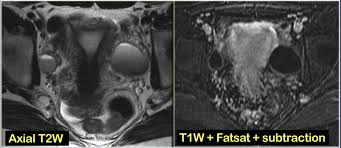

Ovarian cysts with all of the features of ovarian cancer warrant the recommendation of removal of the cyst to definitively determine if it is benign or malignant. The danish cohort study found a link between pcos and endometrial cancer; Stay informed, educate patients, be alert for risk factors, encourage screening, and treat them with compassionate care. Missing a period can be a sign of something minor, or there's a small chance it could be ovarian cancer. Researches have shown that women with pcos have a high risk of ovarian cancer; Around 90% of ovarian cancers occur in women. Why women with this disease may have a higher exposure or higher infection rate is not known. So is there a connection between fibroids and polycystic ovarian syndrome (pcos)? Many symptoms of ovarian cancer are hard to recognise as they are similar to conditions such as irritable bowel syndrome (ibs). Long or irregular menstrual cycles may be a signal of a woman's risk for ovarian cancer, according to a recent study conducted by researchers at the fred hutchinson cancer research center. In other words, the rate of exposure to h. By understanding a patient's family history and lifestyle, the nurse can encourage patients to take action that supports their health and. Likewise, while some research indicates a possible relationship between pcos and ovarian cancer, the human reproduction update suggests that you're no more likely to develop ovarian cancer than someone without pcos.

A pelvic exam, when your ovaries and uterus are checked for size, shape and consistency, can sometimes detect some reproductive system cancers at an early stage. Polycystic ovarian syndrome causes cysts, (also not cancerous), that suddenly occur in one or both ovaries. However, some research has found no relationship between the two. Long or irregular menstrual cycles may be a signal of a woman's risk for ovarian cancer, according to a recent study conducted by researchers at the fred hutchinson cancer research center. Ovarian cysts with all of the features of ovarian cancer warrant the recommendation of removal of the cyst to definitively determine if it is benign or malignant. Ovarian cysts are a common occurrence among women of reproductive age. Likewise, while some research indicates a possible relationship between pcos and ovarian cancer, the human reproduction update suggests that you're no more likely to develop ovarian cancer than someone without pcos. Communities > ovarian cancer > pcos. By understanding a patient's family history and lifestyle, the nurse can encourage patients to take action that supports their health and. Both conditions can disrupt menstrual cycles, cause pelvic pain and impair fertility. However, this risk could be because of possible cysts on the ovaries that may occur in some women with pcos. Learn about the connection between a missed period and ovarian cancer. So basically i don't think that ovarian cancer could be mistaken for polycystic ovaries at this moment but on the other hand patients diagnosed with polycystic ovary syndrome are at risk of getting diabetes, hypertension and increased levels of triglyceride and cholesterol which could cause cardiovascular diseases.